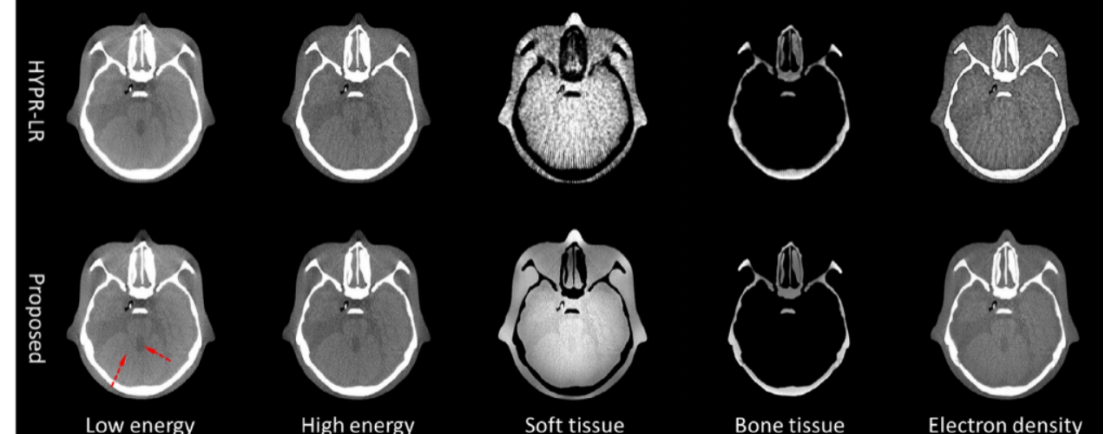

能谱CT现有方法与所提方法的结果对比 第一行是现行方法,第二行是团队提出的新方法

杨益东团队首次提出了图象域双能图像信息矢量化分解的数学算法,结合联合双边滤波,不仅将图像中不同的组织成分精确地区分开来,而且大幅提高了图像的质量。